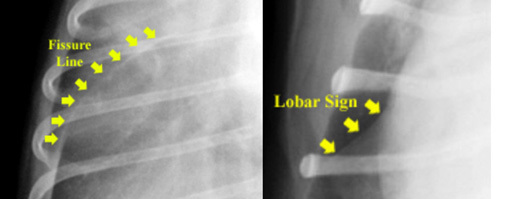

What is meant by a lobar sign?

A sharp line of demarcation between a lung lobe that is opaque (consolidated) and adjacent to one that is aerated.